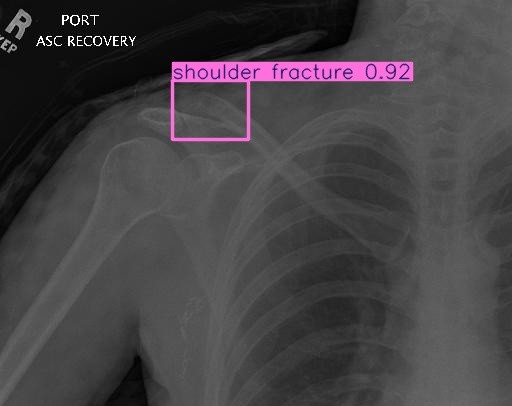

Fracture Detection & Localization

Detect Fractures in Real-Time

Analyze X-rays in real-time to detect fractures and highlight them with Box

Flag potential fracture zones and generate visual overlays to assist radiologists during diagnosis.